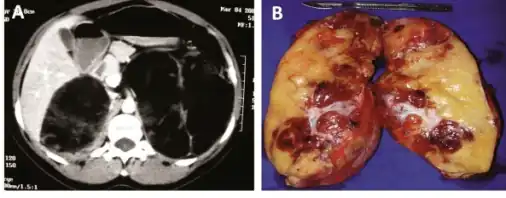

Myelolipomas are usually found to occur alone in one adrenal gland, but not both. They can vary widely in size, from as small as a few millimetres to as large as 34 centimeters in diameter. The cut surface has colours varying from yellow to red to mahogany brown, depending on the distribution of fat, blood, and blood-forming cells. The cut surface of larger myelolipomas may contain haemorrhage or infarction.[1]

The cut surface shows colour variegation from yellow to red to brown depending on the distribution of fat, blood and myeloid elements

a)CT scan showing heterogeneous bilateral myelolipomas b) macroscopic aspect of left adrenal myelolipomas